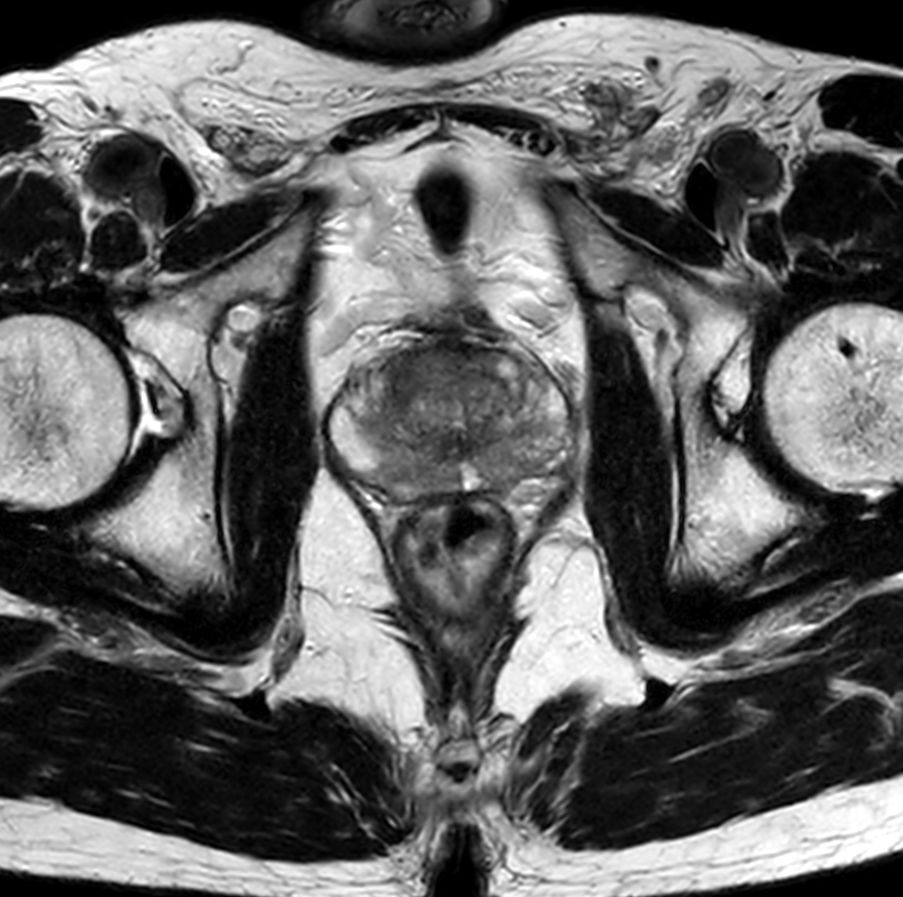

For prostate exams, the MSK M coil can be used in combination with the posterior coil, delivering exceptional quality MR images and high patient satisfaction.

Premium signal-to-noise ratio is achieved via dStream, providing outstanding image resolution.